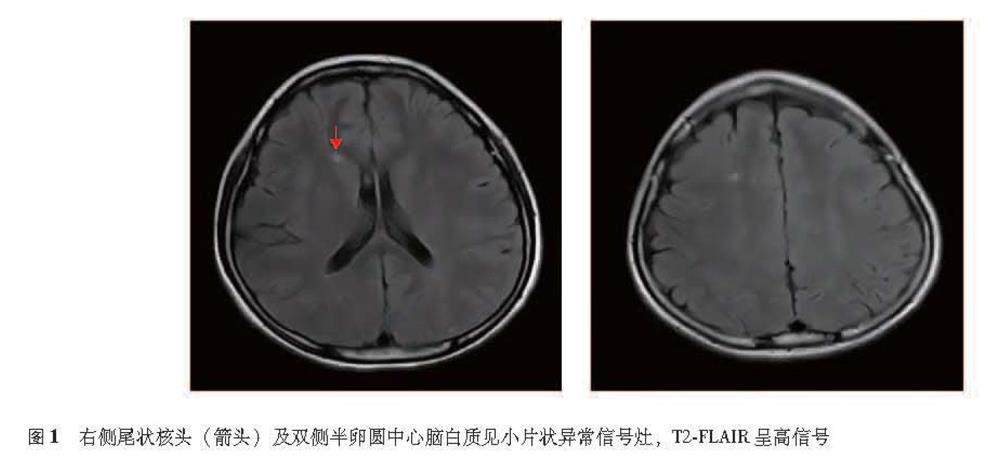

摘要:系统性红斑狼疮合并舞蹈症在国内相对罕见,目前尚无统一的诊断标准及特异性辅助检查,为排除性临床诊断。本文报道暨南大学附属第一医院风湿免疫科2022年1月收治的1例系统性红斑狼疮合并舞蹈症患者的临床资料,并结合近10年国内外相关文献进行复习,总结这些病例的临床特点,以提高风湿免疫科医生对该病的认识。(剩余12313字)